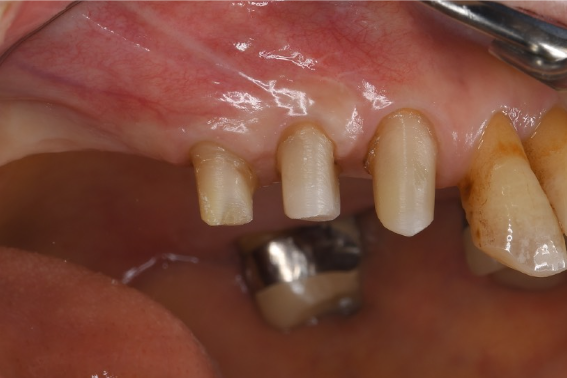

症例3

| 項目 | 詳細 |

|---|---|

| 患者様データ | 50代 男性 |

| 来院時の主訴 | 「左下で噛むと違和感がある。」 |

| 医院の診断 | 左下第二大臼歯の歯根破折 |

| 通院期間 | 9か月 |

| 来院回数 | 12回 |

| 治療費 | 総額:835,000円(税抜) 【内訳】 インプラント埋入手術250,000円、GBR(骨再生手術)150,000円、2次手術+FGG(遊離歯肉移植術)55,000+60,000円、仮歯30,000円、インプラント上部構造(セラミッククラウン)170,000円、隣在歯セラミッククラウンのやりかえ120,000円 |

| リスクと副作用 | 定期的なメンテナンスが必要、術後若干の腫れと痛み |

| ここがこだわりのポイント!☝ | インプラント周囲に角化歯肉と言われる健常な歯肉がなかったので、口蓋からの歯肉移植を行っています💡この角化歯肉がないと、インプラントをしてもうまく歯磨きができないことがあります。 |